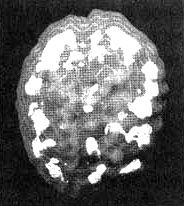

Мозг Сары - маниакально-депрессивный синдром

Трехмерное изображение активного мозга - вид сверху. Обратите внимание на участки повышенной активности, разбросанные по всей поверхности коры.

Провести его оказалось нелегко. Мы пытались провести сканирование три раза. Первые два раза она вырывала из вены иглу, утверждая, что мы хотим ее отравить. В третий раз нам удалось провести обследование, поскольку рядом стояла ее сестра, которая разговаривала с ней на всем протяжении процедуры. Результаты показали повышенную активность в глубокой лимбической системе, но не только. Я обнаружил очаги повышенной активности в левой части мозга и участки выраженного повышения активности по всей коре. Иными словами, в каких-то областях отмечалась повышенная активность, а в других - пониженная. Из своего опыта я знал, что циклические нарушения эмоционального состояния часто сочетаются с очагами повышенной активности в глубокой лимбической системе и с участками повышенной активности по поверхности всего мозга.